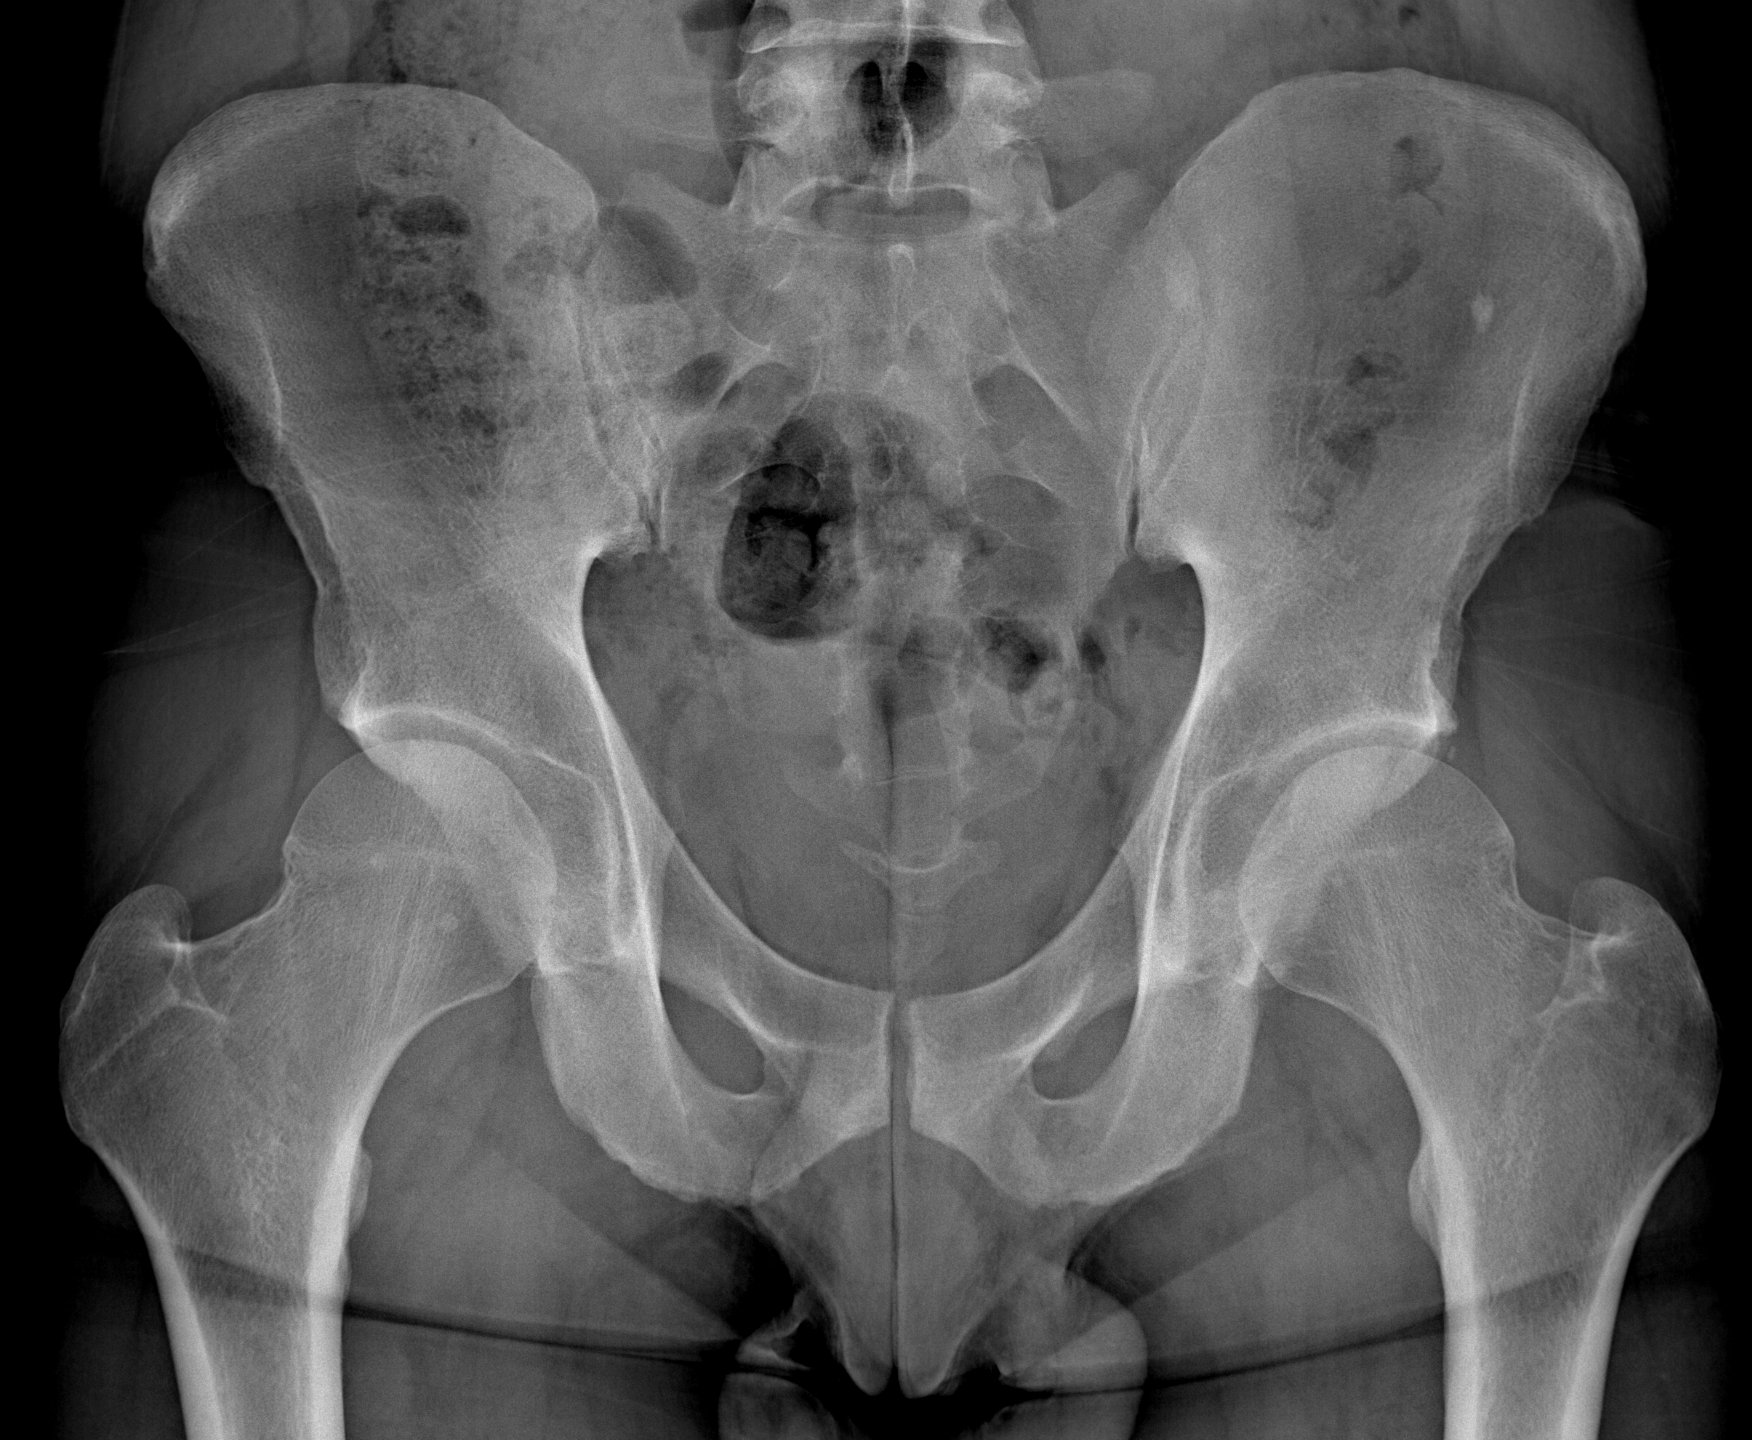

Inoltre la radiologia digitale rappresenta l’indagine di primo livello nello studio di tutte le patologie dell’osso e delle articolazioni.

L’esame radiografico risulta indispensabile per verificare il corretto posizionamento delle protesi articolari (di spalla, di anca, di ginocchio, di gomito) e per monitorare nel tempo la loro condizione.